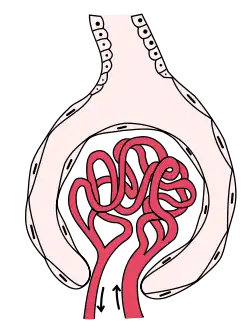

Pathophysiology

The kidney glomerulus filters the blood that arrives at the kidney. It is formed of capillaries with small pores that allow small molecules to pass through that have a molecular weight of less than 40,000 daltons,[33] but not larger macromolecules such as proteins.

In nephrotic syndrome, the glomeruli are affected by an inflammation or a hyalinization (the formation of a homogenous crystalline material within cells) that allows proteins such as albumin, antithrombin or the immunoglobulins to pass through the cell membrane and appear in urine.[15]

Albumin is the main protein in the blood that can maintain an oncotic pressure, which prevents the leakage of fluid into the extracellular medium and the subsequent formation of edemas.

As a response to hypoproteinemia, the liver commences a compensatory mechanism involving the synthesis of proteins, such as alpha-2 macroglobulin and lipoproteins.[15] An increase in the latter can cause the hyperlipidemia associated with this syndrome.